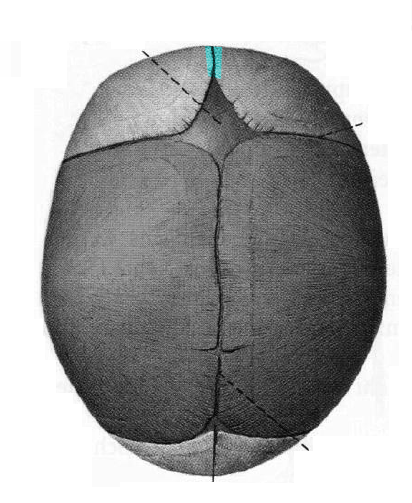

sutura frontalis

-küçük çocuklarda os frontaleda ayrık olan kısımlarının arasındaki dikiş izine benzer

eklemdir.

-6. yaşından sonra kemikleşerek kaybolur.